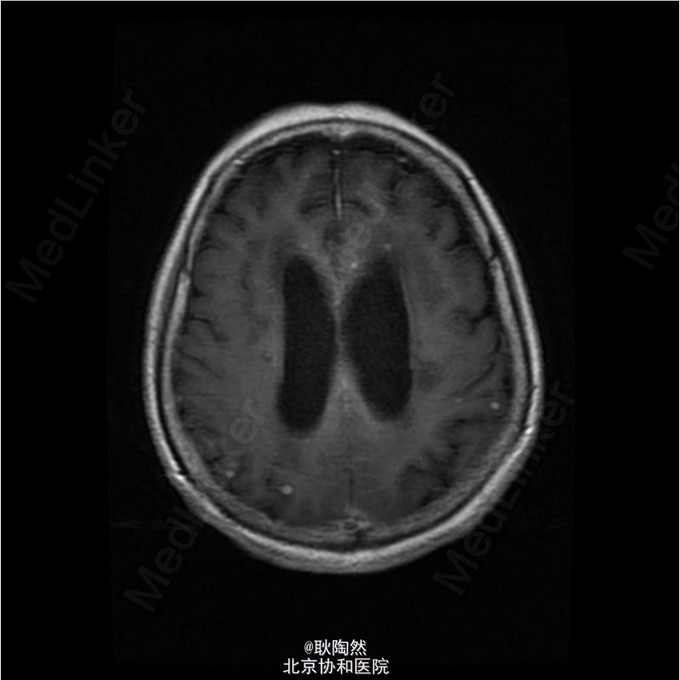

患者75岁老年女性,因“间断发热1年余,乏力、少语2周”于2014-12-25入院治疗。 2013年起患者无明显诱因出现发热,每日午后温度渐高,Tmax39℃,次日凌晨可降至正常。伴乏力,无盗汗、畏寒寒战、咳嗽咳痰等表现。外院胸部CT提示“肺部感染”,予莫西沙星治疗后体温正常。 2013-3患者出现T12椎体骨折,行手术治疗,术前有发热表现,予莫西沙星抗感染治疗后体温正常。2014-5因再次出现腰痛复诊,因前次手术窦道(左髂)迟迟未愈合,于左髂处取活检:坏死性肉芽肿,伴死骨形成,可见多核巨细胞及类上皮细胞,抗酸染色(-),不除外结核。 后患者间断发热。2014-8胸部CT示:右上肺尖后段、右中叶外侧段、左下肺外侧段散在片絮、云雾状不规则高密度灶,密度不均,提示感染;纵膈内未见肿大淋巴结。右肺病灶行肺穿活检:可见肺组织及部分横纹肌组织,肺组织变性坏死,周围小灶肉芽肿形成,纤维组织增生,慢性炎症细胞浸润,部分细胞增生。抗酸(-),PAS(-),六胺银(-)。 2014-12起患者出现神情淡漠,懒言少语,乏力加重,不能坐起或下床。遂入我科。 入我科后查PPD皮试:(+++);血T-SPOT.TB:MLC+IFN(A) 36SFC10^6MC,MLC+IFN(B) 704SFC10^6MC; 胸腹盆CT(平扫):右肺上叶后段胸膜下肿块大致同前;两上肺及右中肺粟粒样结节并两肺多发斑片索条及散在钙化灶,考虑结核性病变;两肺门多发钙化灶,纵隔多发淋巴结;双侧胸膜增厚,大致同前;胸8-腰4 椎体多发内固定器,部分椎体骨质破坏,可为椎体结核术后改变;胸11-腰3 椎体左旁多发低密度影并环形强化,考虑椎旁脓肿;骶骨前方、直肠后方片状低密度影,渗出性改变不除外。 行腰穿:脑脊液压力为88mmH2O。脑脊液常规:外观 无色透明,细胞总数 12*10^6/L,白细胞总数 0*10^6/L,单核 0,多核 0;脑脊液生化:CSF-Pro 0.76g/L,CSF-Cl 115mmol/L,CSF-Glu 1.5mmol/L。脑脊液抗酸染色(-)、脑脊液结核、非结核分枝杆菌DNA(-);脑脊液T-SPOT.TB:MLC+IFN(A) 24 SFC10^6MC,MLC+IFN(B) 132 SFC10^6MC;脑脊液细胞学:结论:淋巴细胞性炎症,WBC 1000/0.5ml,AL 阳性(+),AM 阴性(-),PC 阴性(-),TC 阴性(-),RBC -,CL ++,LY% 90%,MONO% 5%,NEUT% 5.000%; 考虑患者为播散性结核感染,有肺、骨、中枢神经系统受累。予异烟肼、利福喷丁、乙胺丁醇、拜复乐四联抗结核治疗。